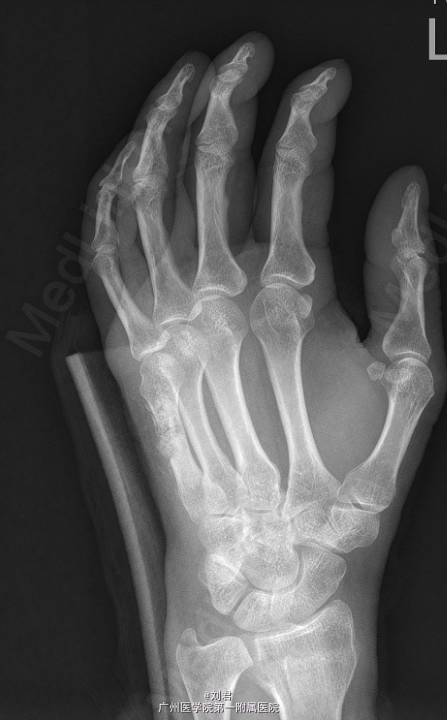

患者,女,51岁,因“摔伤致左腕肿痛伴活动障碍7天”入院。 患者7天前摔伤,左掌着地,致昨晚疼痛,疼痛为持续性,较剧,能忍,伴左腕活动障碍.

左腕石膏托固定,左腕肿胀,无明显畸形,压痛明显,左腕活动障碍,左手各指血运好,感觉正常,活动可。

初步诊断:1、 左桡骨远端骨折,2、左手第5掌骨软骨类肿瘤。在臂丛复合静脉麻醉下行“左掌骨内生软骨瘤切除术”,手术过程顺利,术后予以对症治疗。

体温正常,伤口愈合可,无异常渗出,敷料包扎干燥,石膏固定中,摘除后关节活动可,左手末梢感觉血运无殊.